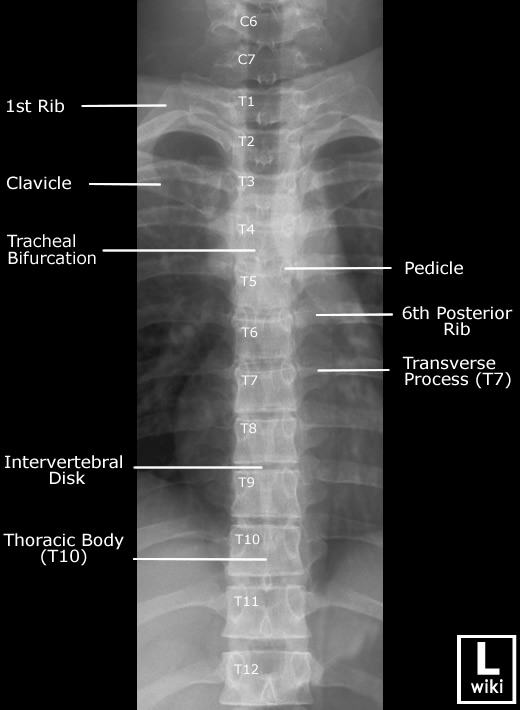

| AP view (Cervical) | AP view (Thoracic) |

![]() |